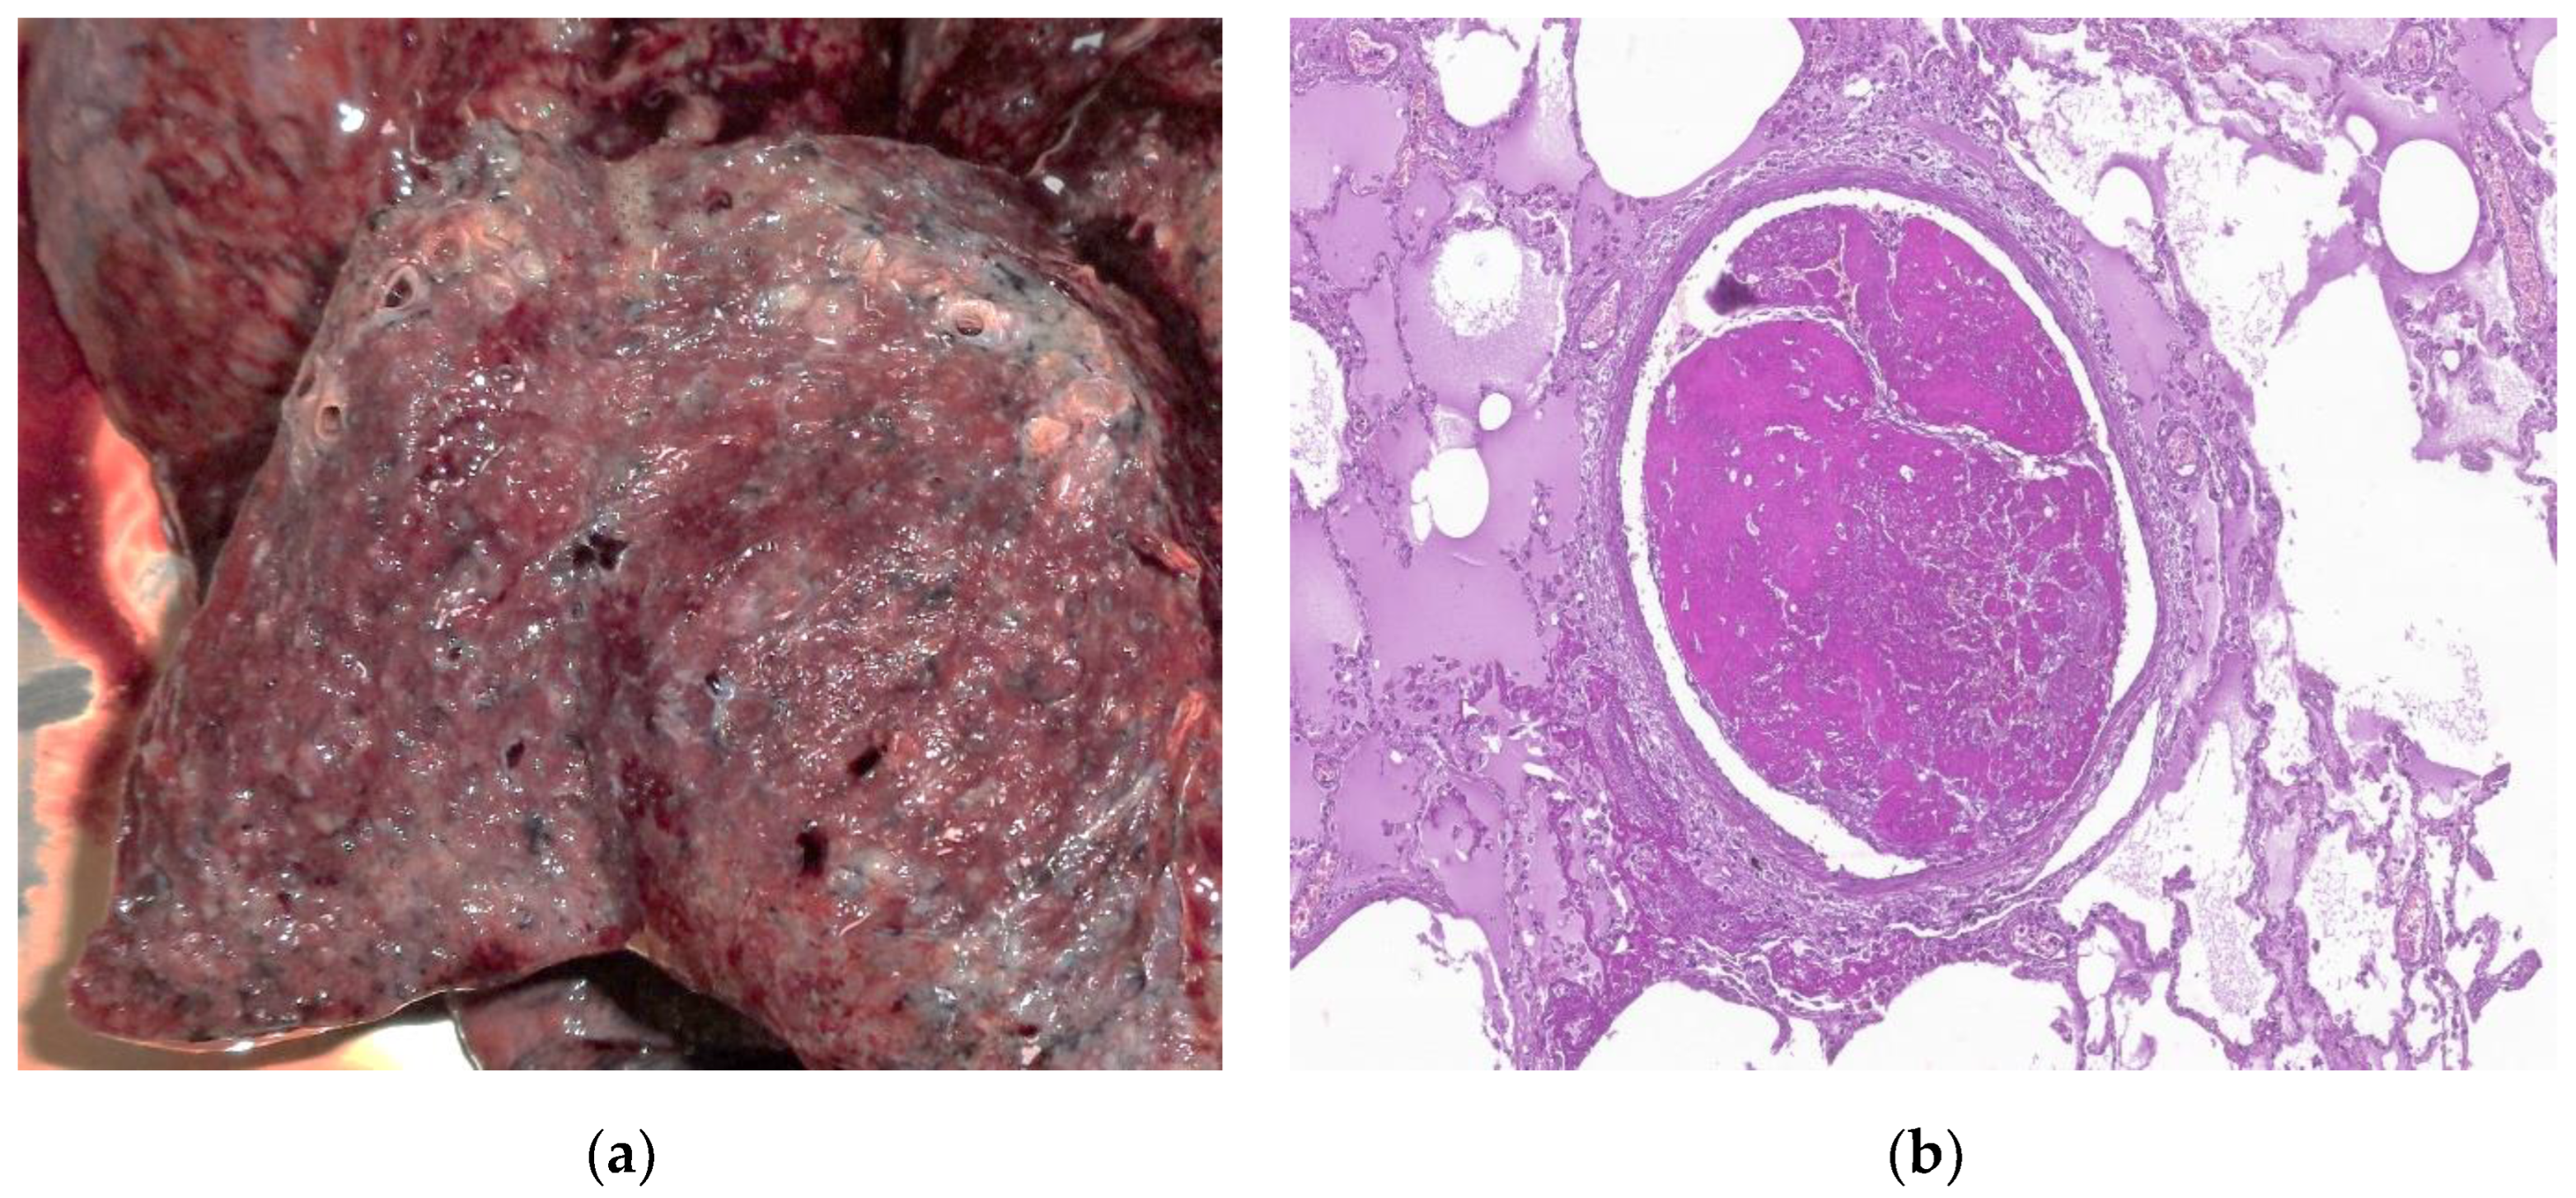

7. Histopathologic characterization

- Chen, J.Y.; Qiao, K.; Liu, F.; et al. Lung transplantation as therapeutic option in acute respiratory distress syndrome for coronavirus disease 2019-related pulmonary fibrosis. Chin Med J (Engl) 2020, 133, 1390–1396. [Google Scholar] [CrossRef]

- Bharat, A.; Querrey, M.; Markov, N.S.; Kim, S.; Kurihara, C.; Garza-Castillon, R.; Manerikar, A.; Shilatifard, A.; Tomic, R.; Politanska, Y.; et al. Lung transplantation for patients with severe COVID-19. Sci. Transl. Med. 2020, 12. [Google Scholar] [CrossRef]